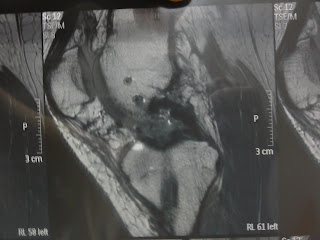

13 months post-op and I feel like it should be at least a little better than it is. It hurts most of the time, I can't do anything significant - not even strength! - and it honestly gives me more trouble than pleasure right now. Funny thing is that in my head I'm imagining it'll be fine once I hit Europe - but why on earth would it???